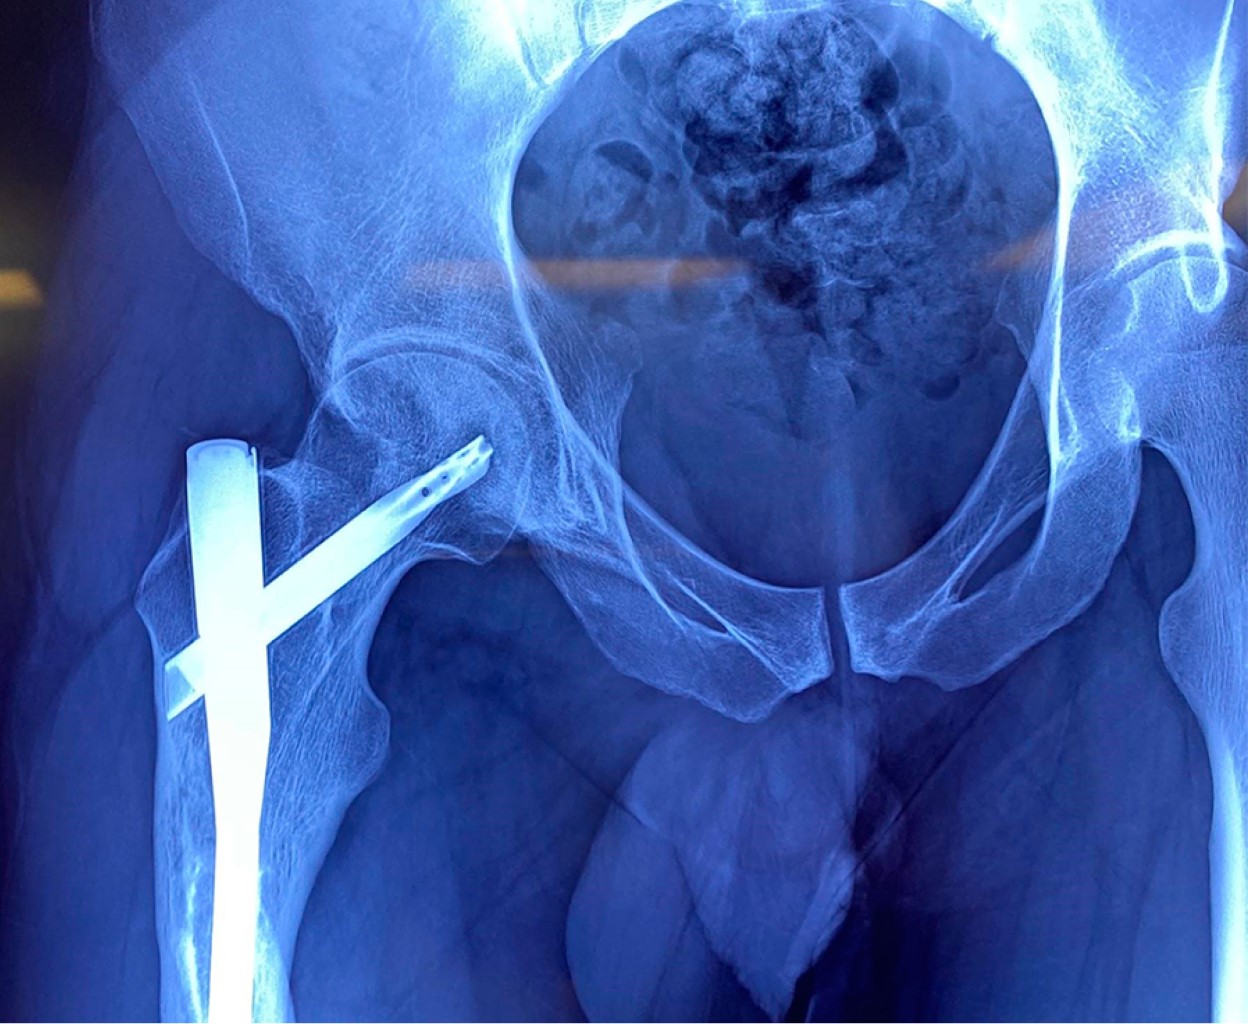

Las radiografías de cadera derecha en proyección anteroposterior (Figura 1) y lateral (Figura 2), así como radiografías de eje mecánico (Figura 3), evidenciando fractura consolidada de fémur diafisario derecho, acortamiento de 2.04 cm de miembro pélvico derecho a expensas de fémur y clavo centromedular anterógrado de entrada trocantérica. La radiografía lateral de cadera derecha revela protrusión posterior de la hélice del clavo centromedular a través de la cabeza femoral encontrándose en contacto con pared acetabular posterior. Este contacto condiciona erosión de pared acetabular alrededor de la protrusión.

Figura 1

Figura 2